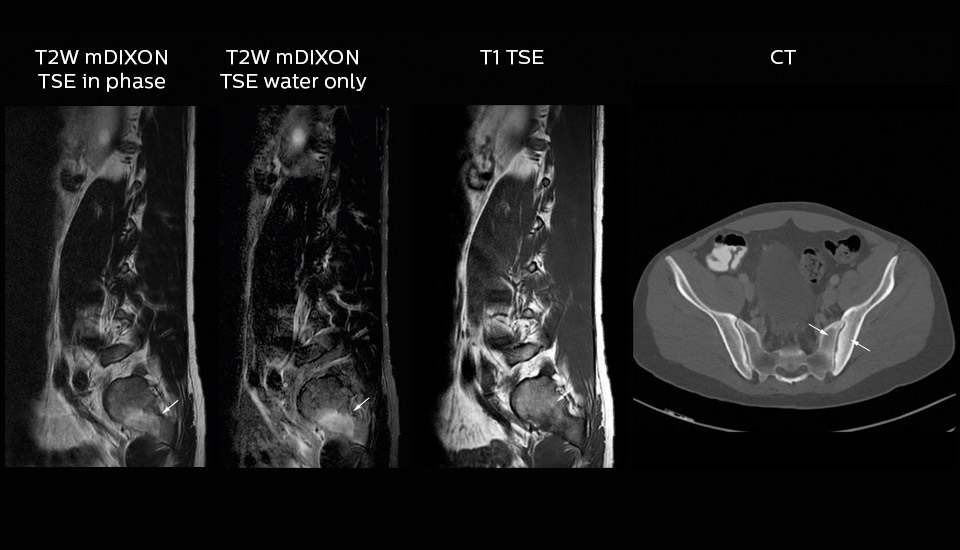

“In our lumbar spine MRI, the value of mDIXON TSE is so obvious. Normally we perform T1 and T2 scans in sagittal and transverse orientation.It used to take too much time to add a sagittal T2 with good fat suppression.But now, using mDIXON TSE, we get the sagittal T2 fat suppressed images ‘for free’, that is: without adding time.” “Diagnostically that is a great benefit. I sometimes see abnormalities in the fat suppressed sagittal T2 that would be quite challenging to notice in the T2 without fat suppression. There have been several diagnoses that I could make easier because of our exam setup with mDIXON TSE, such as sacrum insufficiency fractures and sacroileitis; these were more challenging with our previous exam setup.”